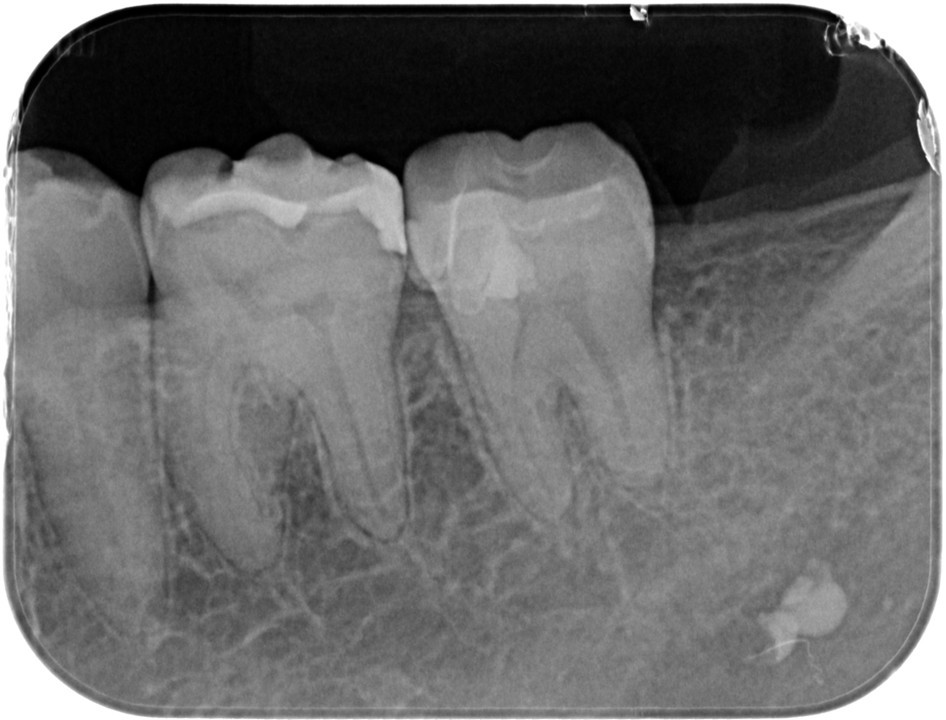

術後7年以上経過して状態は安定している(図13)。

術後7年との比較 左:2017.11.09 右:2024.11.23

近心髄角付近にはデンチィンブリッジ形成による象牙質様の不透過像の生成が確認できる

(図14)VPT症例

露髄面の大きさは関係なく正常な歯髄が存在し、健全象牙質上にMTAのセメント層が3ミリ確保できれば良好な結果が得られる

(図15)術後5年経過

髄角付近にデンティンブリッジ形成による硬組織の生成が確認できる